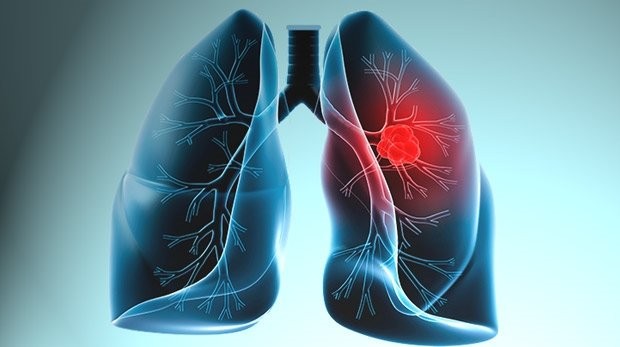

Akciğer kanseri akciğerdeki hücrelerin kontrolsüz çoğalması ile başlayan bir hastalıktır. Kontrolsüz çoğalan bu hücreler normal akciğer hücresi gibi çalışmaz ve normal gelişme göstermezler. Tam tersine akciğer dokusunda bozulmalara neden olarak akciğer fonksiyonlarını etkilerler.

Vücuttaki tüm hücreler DNA dediğimiz genetik materyal içerir. Normal olgun hücreler ikiye bölünerek sağlıklı DNA yapısında iki orijinal yeni hücre oluşturur. Vücut bu şekilde kendini yeniler. Kanser DNA dediğimiz moleküllerde; çevresel faktörler, sigara içimi, asbest soluma, radon gazına maruziyet gibi nedenler sonucu bozulma ile başlayan bir süreçtir. İleri evrelerde fonksiyonu bozulmuş farklı hücreler kan ve lenf yolu ile başka organlara taşınarak yerleşirler ve metastaz denilen süreç başlar.

İki ana tıp vardır. Küçük hücreli ve küçük hücreli dışı akciğer kanserleri. Evreleme ise kanserin yayılması ve büyüklüğü ile doğru orantılıdır.